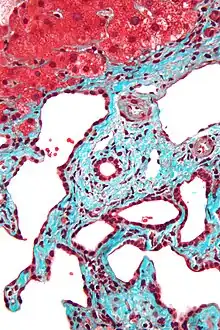

Histopathology of a bile duct hamartoma, high magnification, H&E stain. It shows typical features of bile duct hamartoma: